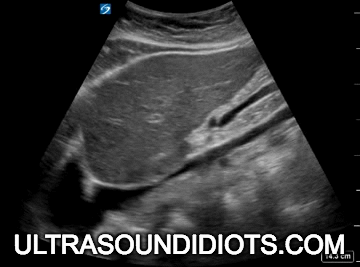

Echo Subcostal Exams